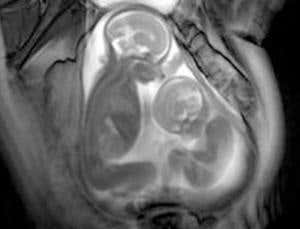

Separate development (Image: Marisa Taylor-Clarke, Robert Steiner MR Unit, Imperial College)

They might share the same DNA and cramped living space, but as these images reveal, life is anything but identical for unborn twins.

This unprecedented glimpse into their inner world is afforded through a recently developed form of magnetic resonance imaging (MRI), which is being turned on twins for the first time.

Whereas conventional MRI takes snapshots of thin slices of the body as it penetrates through it, so-called cinematic-MRI takes repeated images of the same slice, then stitches them together to create a video. This means that a moving structure such as a fetus – or several fetuses – can be visualised in unprecedented detail.